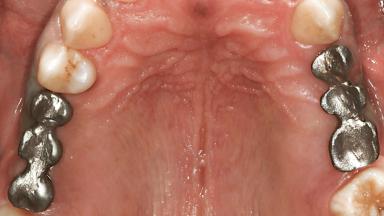

Replacement of Multiple Teeth in a Partially Dentate Posterior Maxilla and Mandible with Fixed Dental Prostheses Using a Conventional Loading Protocol

In the summer of 2002, a 42-year-old female patient was referred to the University of Geneva for the replacement of posterior maxillary and mandibular missing or non-restorable teeth.The patient’s medical history revealed no significant findings,and she was in good general health.Her dental history included recurrent decay that led to the loss of several posterior teeth. The patient showed no history of periodontal disease. At the extraoral examination, the patient presented normal physiognomy with normal facial and lip support and homogenous distribution of the facial thirds. At full smiling, the patient displayed an average lip line, and a tooth gap was slightly visible in the left maxilla. Small diastemas were present between the anterior maxillary teeth.